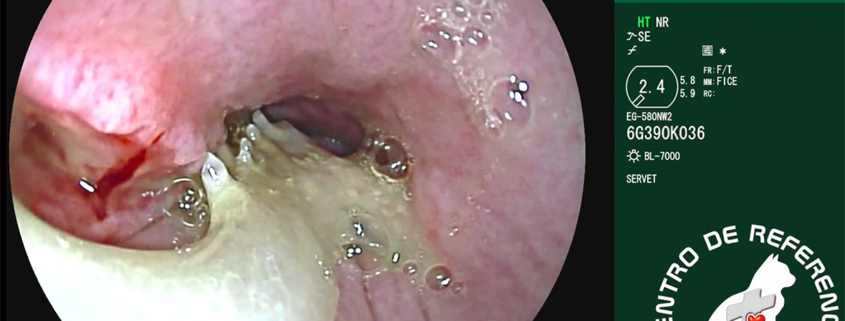

Endoscopia aguja estómago – Servet Urgencias